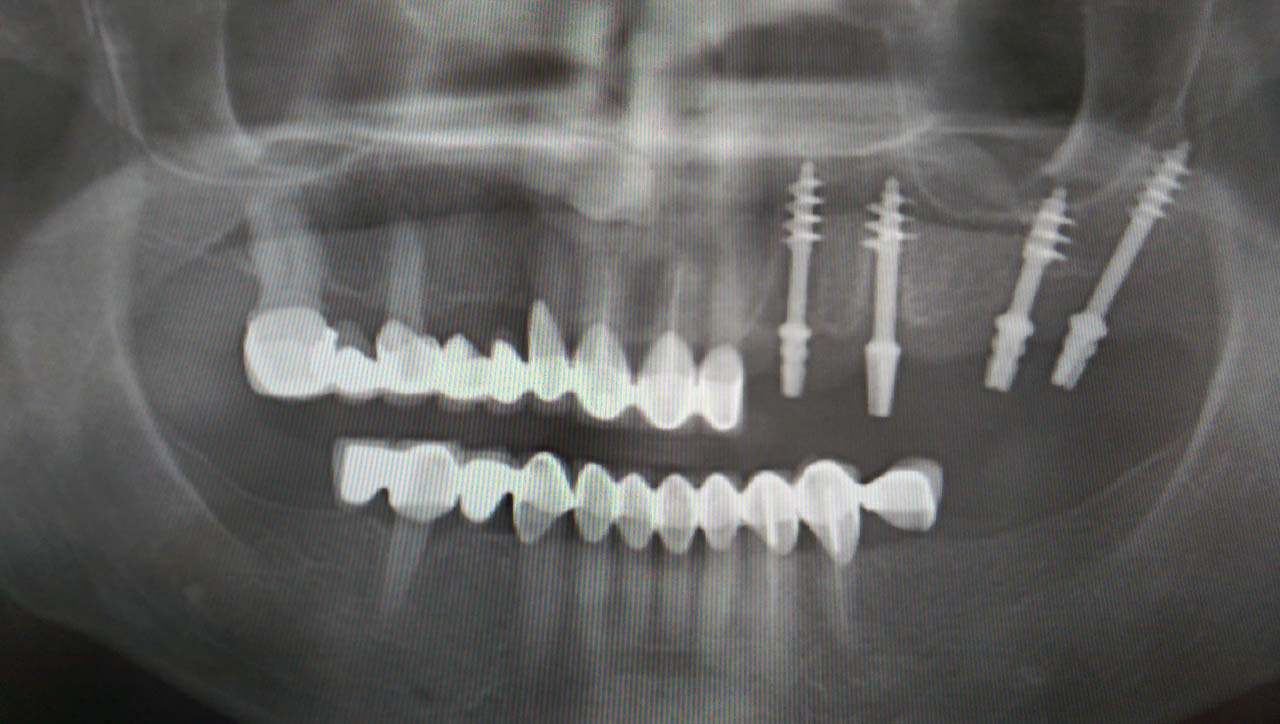

2 nap alatt varázsoltuk ezt a szép esztétikus alsó, felső körhídat implantátumokkal megtámasztva a korábban elhanyagolt szájba. Az 1. nap 26 fogat távolítottunk el, mert annyira rossz állapotban voltak, és rögtön azonnal terhelhető IHDE svájci implantátumokat raktunk be, fentre 8, lentre 6 darabot. A sebeket összevarrtuk és intraorális szkennerrel digitális lenyomatot vettünk. 2 nap múlva pedig beragasztottuk a kész PMMA műanyag körhidakat. Dr. Kelemen Péter és a Symbion Fogtechnika munkája.

Teljes fogatlanság helyreállítása 2 nap alatt azonnal terhelhető svájci IHDE implantátumokkal és PMMA műanyag hidakkal. Intraorális szkennerrel vettünk lenyomatot az implantáció után, és erre a digitális mintára készítette el a fogtechnika a hidak digitális tervezését, majd faragta ki műanyagból. Ezt a gyors munkát az azonnal terhelhető implantátumok és a digitális lenyomat, tervezés segítségével tudtuk megcsinálni mindössze 2 nap alatt. Dr. Kelemen Péter és a Symbion Fogtechnika munkája.